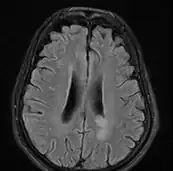

MRI brain: cryptococcus -

Cryptococcal meningitis (infection of the meninges, the tissue covering the brain) is believed to result from dissemination of the fungus from either an observed or unappreciated pulmonary infection. Often there is also silent dissemination throughout the brain when meningitis is present. Cryptococcus gattii causes infections in immunocompetent people (fully functioning immune system), but C. neoformans v. grubii, and v. neoformans usually only cause clinically evident infections in persons with some form of defect in their immune systems (immunocompromised persons). People with defects in their cell-mediated immunity, for example, people with AIDS, are especially susceptible to disseminated cryptococcosis. Cryptococcosis is often fatal, even if treated.[19]

The immune reconstitution inflammatory syndrome (IRIS) has been described in those with normal immune function with meningitis caused by C. gattii and C. grubii. Several weeks or even months into appropriate treatment, there can be deterioration with worsening meningitis symptoms and progression or development of new neurological symptoms. IRIS is however much more common in those with poor immune function (≈25% vs. ≈8%).Magnetic resonance imaging shows increase in the size of brain lesions, and CSF abnormalities (white cell count, protein, glucose) increase. Radiographic appearance of cryptococcal IRIS brain lesions can mimic that of toxoplasmosis with ring enhancing lesions on head computed tomography (CT). CSF culture is sterile, and there is no increase in CSF cryptococcal antigen titre.